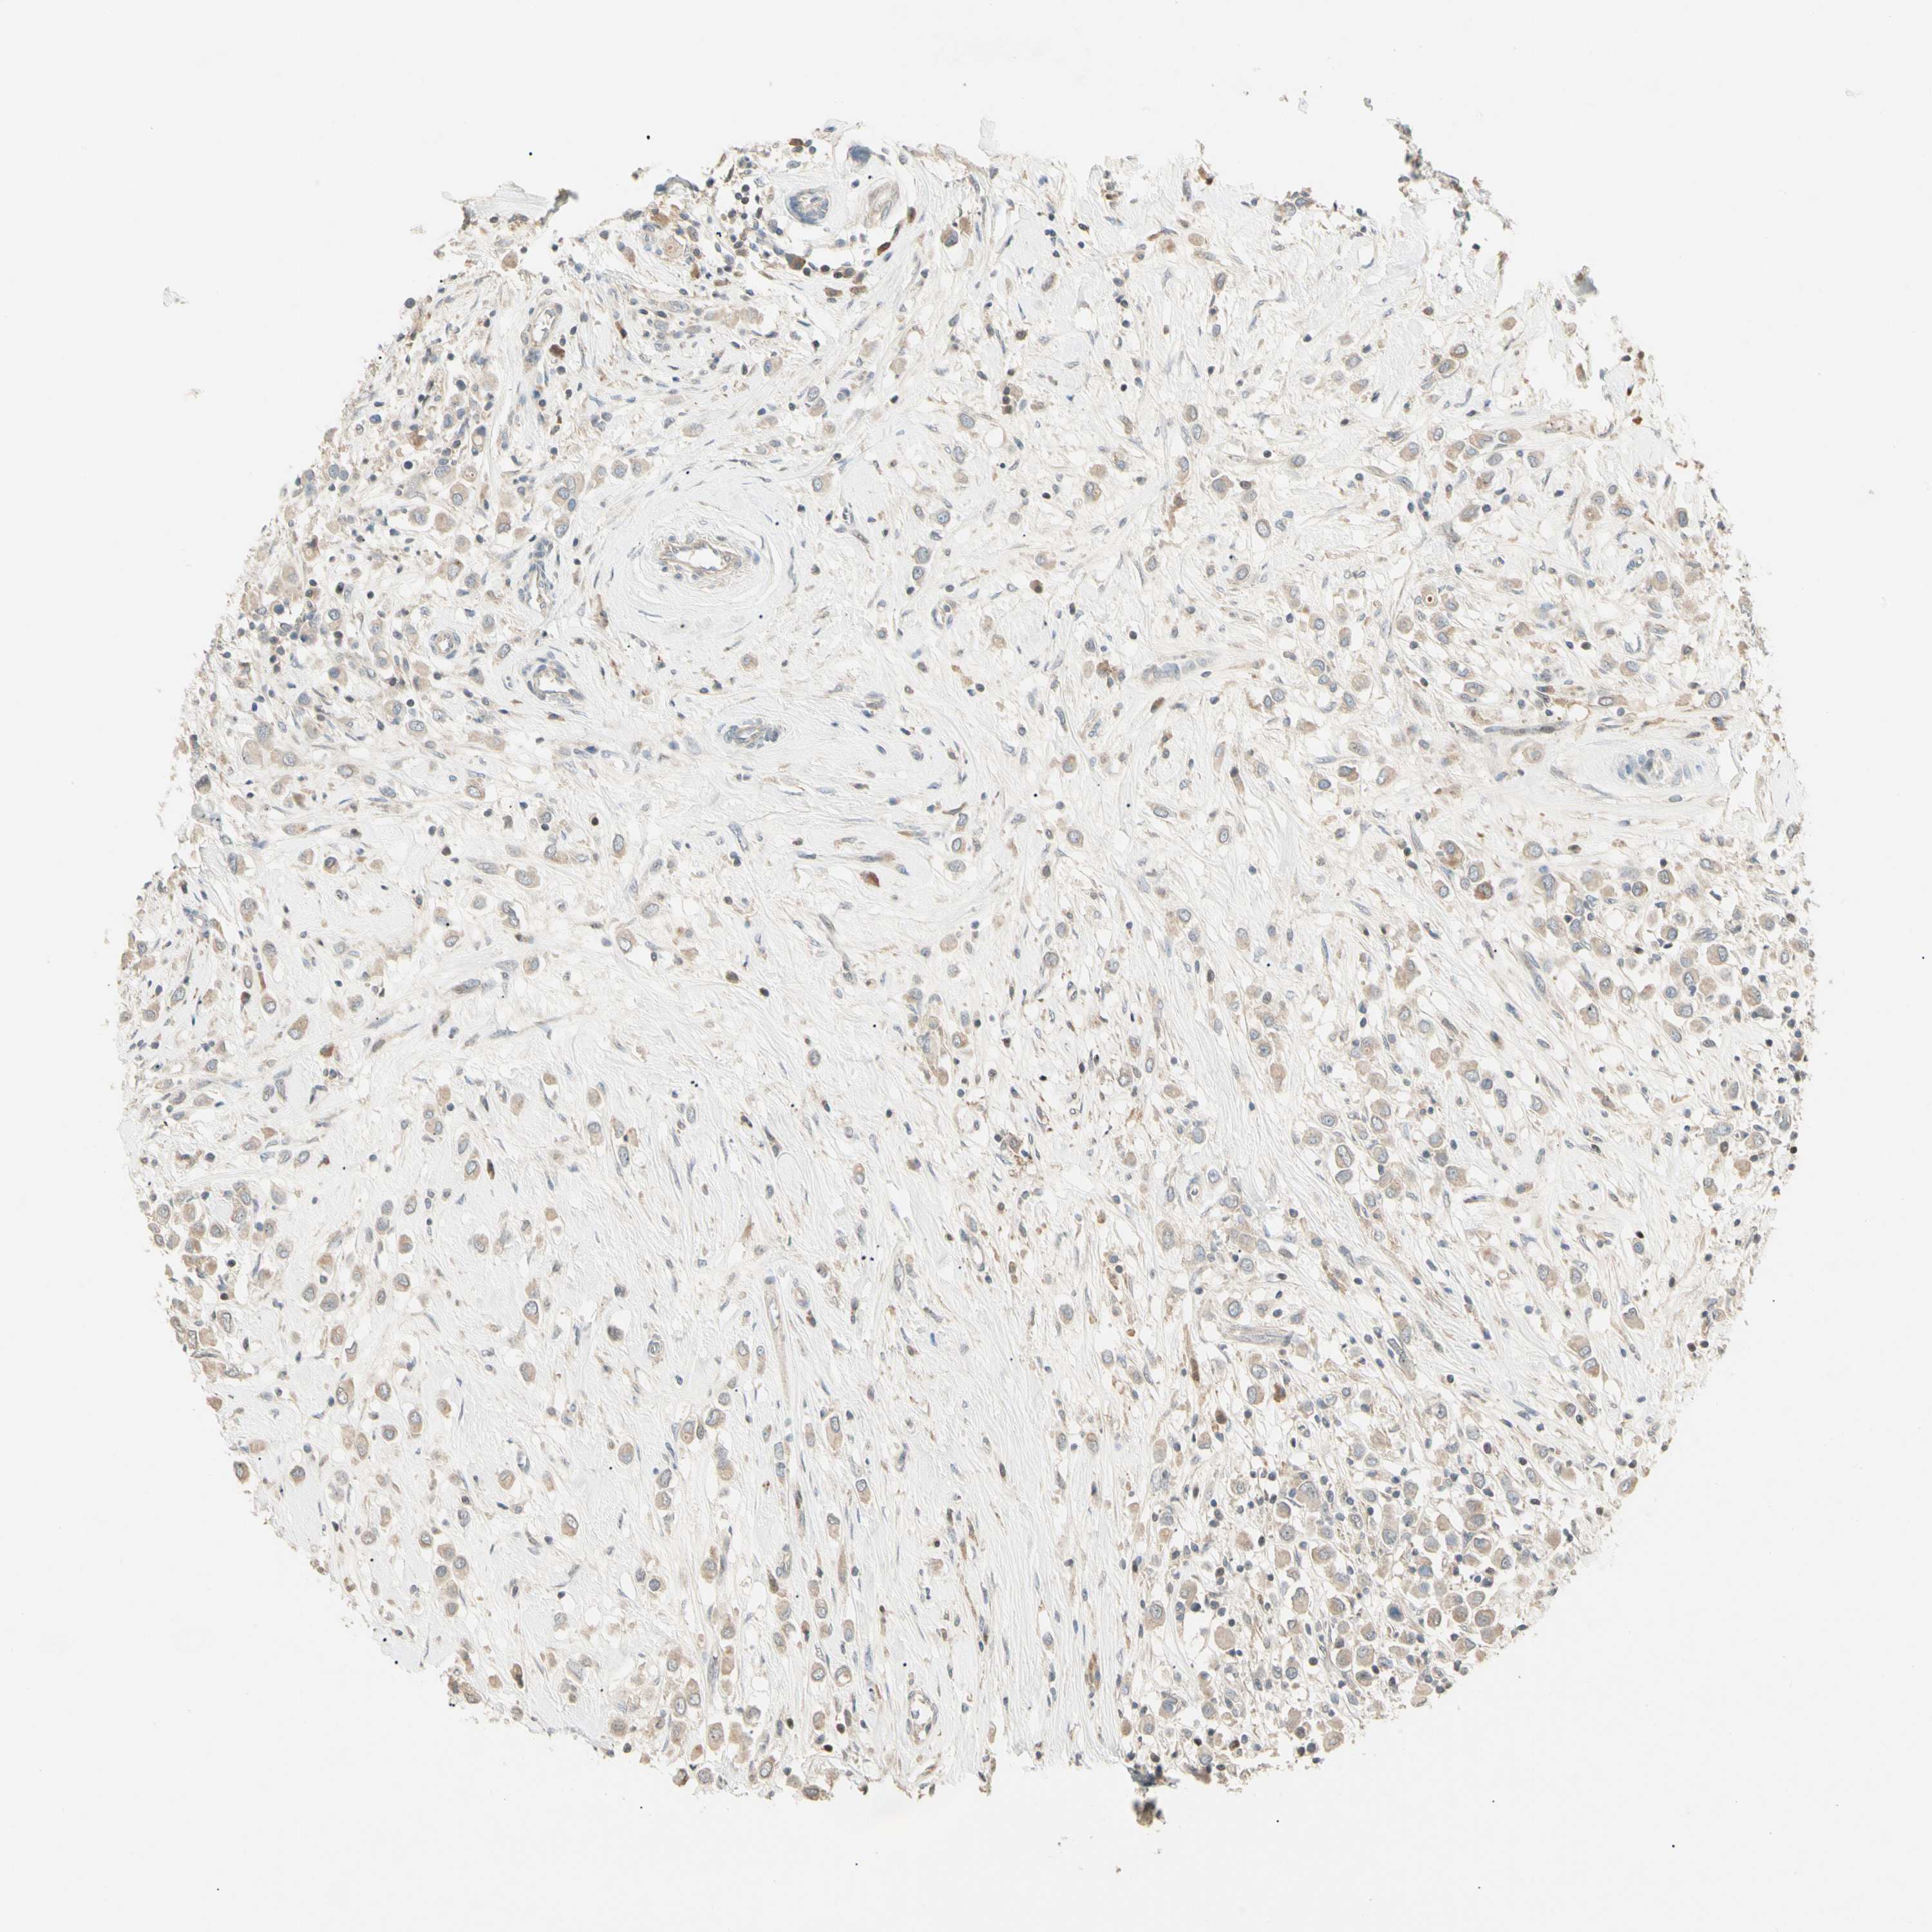

CANCER BREAST CANCER Show tissue menu

BRCA TCGA BRCA VALIDATION PROTEIN EXPRESSION